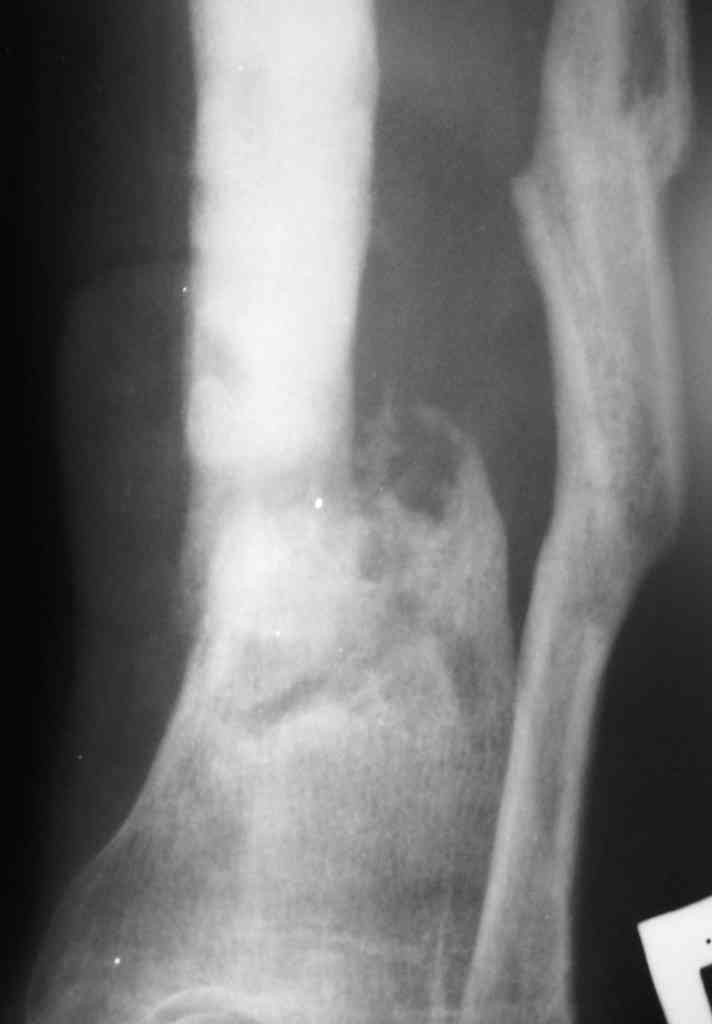

Коротко анамнез: травма в 2004 г. - открытый оскольчатый перелом н/3 голени, имелась рана 4х5 см. по передне-внутренней поверхности. Заживление раны вторичным натяжением. Сращения в АВФ нет. В 2005 г. в нашей клинике произведена костная свободная аутопластика с наложением АВФ. В послеоперационном периоде некроз в области старого рубца 2х3 см., тогда же произведена кожная аутопластика на питающей ножке. Сращения в течение 6 мес. нет, аппарат снят.

В 2006 г. произведена костная аутопластика на сосудистой ножке, иммобилизация гипсовой повязкой. На данный момент признаков консолидации нет.

Периодически у пациента возникают явления дерматита на применение местно лекарственных препаратов на голени, периодически открывается точечный свищ по передней пповерхности в проекции ложного сустава с серозно-гнойным отделянмым.

Укорочение конечности на 4,5-5,0 см., растройств чувствительности нет. При ходьбе конечность нагружает практически полностью при использовании тутора и ортопедической обуви. Внешний вид и R-гр. на фото. У больного еще пока сохранился настрой на лечение.